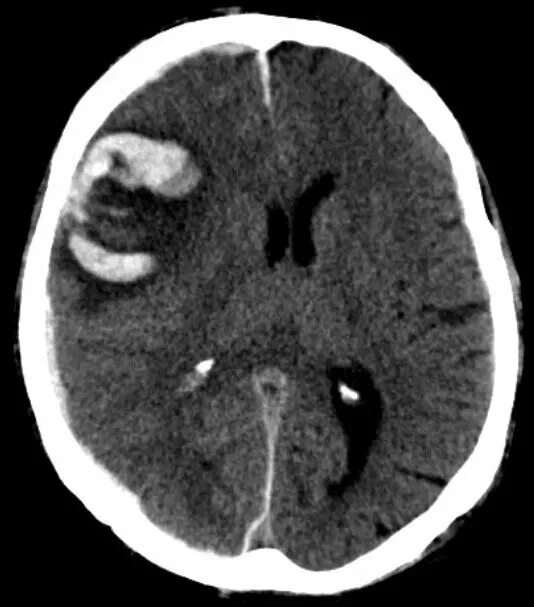

Гематома лобной